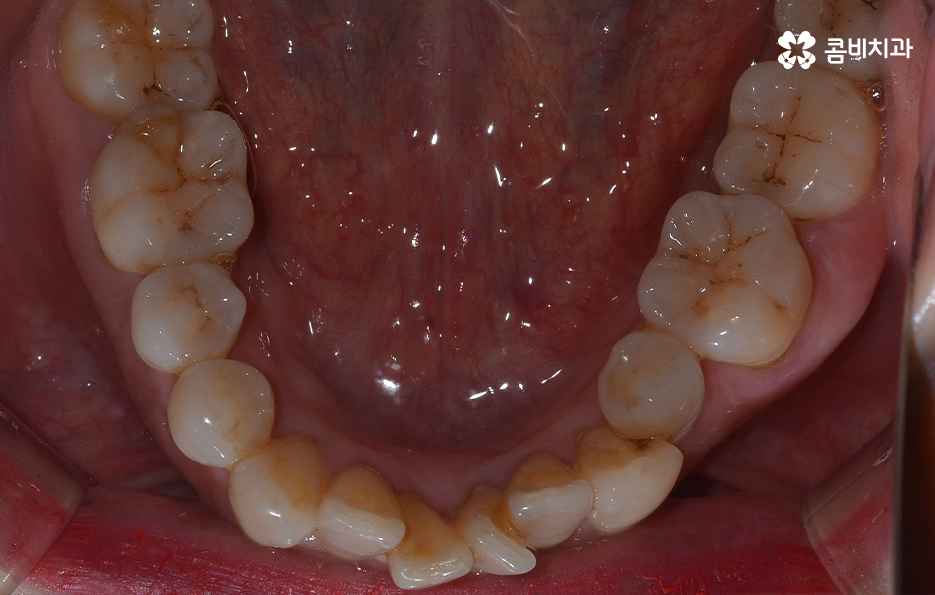

오늘 보시는 교정 사례의 경우를 보시면 아랫니의 틀어짐도 크지만 측면 사진으로 보시면 치열로 인해 돌출입에 영향을 준다는 사실도 알 수 있어요. 즉 치열과 함께 돌출입도 함께 고치고 싶어하기 때문에 치열도 재배열 하지만 치아 안쪽으로 넣어서 입술라인과 얼굴형으로 볼 때도 돌출입도 치료하는 치료 계획을 세웠기 때문에 작은 어금니 발치를 통한 치아의 이동 공간을 확보한 사례로 볼 수 있어요